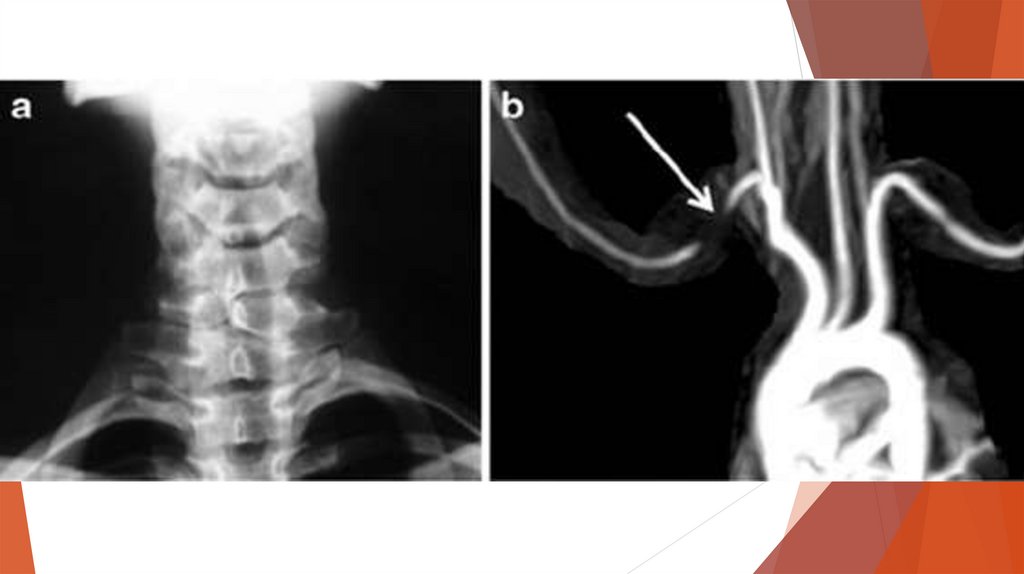

Диагностика

•Электромиография

•Рентгенография

•УЗИ

и КТ